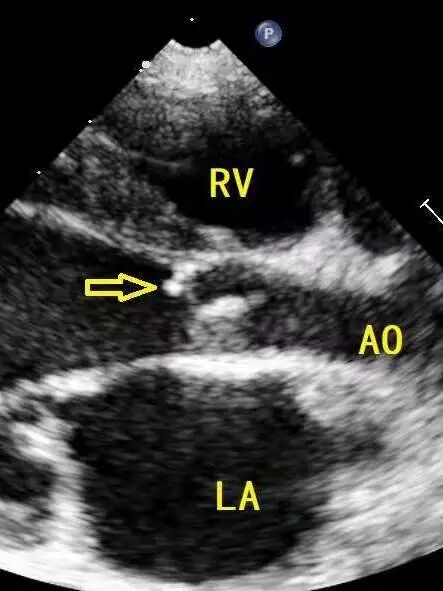

术前超声

楚楚一岁多的时候,因为呼吸道感染,就诊于当地医院,超声提示动脉导管粗大、主动脉瓣下隔膜、二尖瓣的关闭不全。

粗大的动脉导管,加上主动脉瓣下的隔膜,在两种畸形的共同作用下,同时增加了左心室的后负荷和前负荷,导致楚楚的左心室和正常成年人的左心室一样大。尽管心脏病情严重,但楚楚的总体发育并未受到影响,直到最近,孩子开始持续的胸闷,心功能也越来越差,于是一家人辗转来到北京安贞医院寻找解决办法。